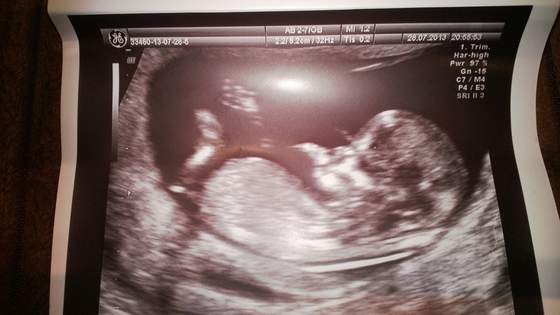

Zobacz załącznik 574849Zobacz załącznik 574850Zobacz załącznik 574851Zobacz załącznik 574852Zobacz załącznik 574853